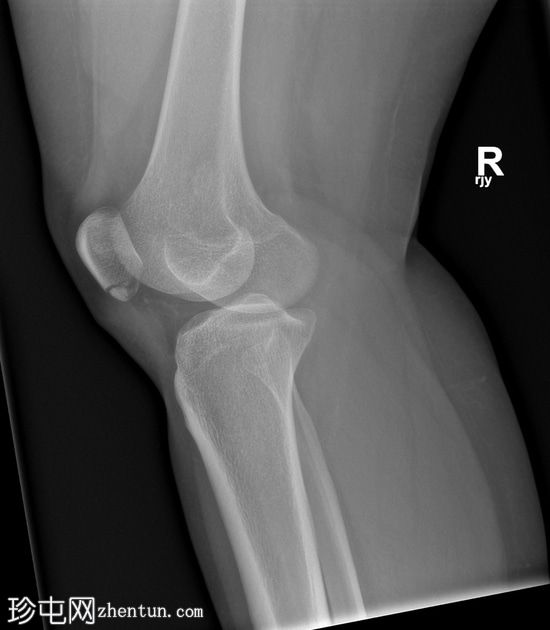

X光片

斜位

髌骨下极横向骨折。髌腱影伴有软组织肿胀,提示创伤性髌腱炎。

髌骨撕脱性骨折通常发生在下极,属于关节外骨折。这类损伤最常见于青少年和年轻人,通常由膝关节突然过度屈曲引起。从生物力学角度来看,它们与髌腱断裂类似。